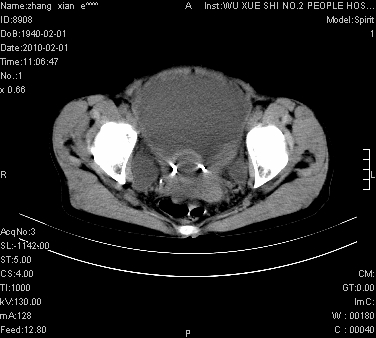

标题: CT24434:70岁 女 腹胀,腹水原因待查 [打印本页]

标题: CT24434:70岁 女 腹胀,腹水原因待查

大量腹水,脾脏囊性占位,子宫颈占位,右侧腹股沟淋巴结肿大,建议+c,先查妇科。

腹盆腔大量积液,子宫增大,子宫颈增大外形不规则,内见低密度影,膀胱后壁显示不清,右腹股沟肿大淋巴结,脾脏囊性占位,子宫颈占位,子宫颈癌?建议增强。

腹盆腔大量积液,子宫增大,子宫颈增大外形不规则,内见低密度影,膀胱后壁显示不清,右腹股沟肿大淋巴结,脾脏囊性占位,子宫颈占位,子宫颈癌?建议增强。支持!